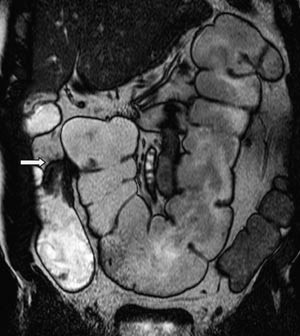

Bruk av sonde gir god utvidelse av både jejunum og ileum (fig 2). Duodenum blir vanligvis ikke fylt med væske fordi sondeballongen hindrer refluks. Av og til vil heller ikke proksimale jejunum bli fremstilt fordi sonden vandrer i distal retning. Den største ulempen med metoden er likevel nedleggelsen av sonden. Pasientene opplever dette som ubehagelig, og prosedyren innebærer fortsatt noe strålebelastning. Det er derfor stor interesse for MR-undersøkelse av tynntarm med oral kontrast.

Vår erfaring med MR av tynntarm med oral kontrast er at metoden gir en god utvidelse av ileum. Bulbus duodeni er også ofte væskefylt, men det er vanskeligere å få resten av duodenum og proksimale jejunum optimalt utvidet (fig 3). En annen ulempe med MR av tynntarm med oral kontrast er ventrikkelretensjon (fig 4). Dette hemmer væskefylling av tarmen, og pasientene kan bli kvalme.